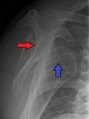

خلع أمامي للكتف الأيسر.

الكتف المخلوع أو خلع الكتف، هي حالة طبية تحدث عند انفصال عظمة العضد عن مفصل الكتف.[2] وتشمل أعراض خلع الكتف آلام في الكتف وعدم استقراره.[2] وتشمل المضاعفات المحتملة لخلع الكتف آفة بانكارت، آفة هل-ساكس، تمزق الكفة المدورة، أو إصابة العصب الإبطي.[1]

عادة ما يحدث خلع الكتف نتيجة لسقوط الشخص على ذراعه وهي ممدودة أو سقوطه على الكتف.[4] عادة ما يعتمد التشخيص على العلامات الظاهرة على الحالة ويتم التأكد عن طريق التصوير بأشعة إكس.[2] تصنف حالات خلع الكتف إلى خلع أمامي، خلفي، سفلي، وعلوي والأكثر شيوعاً هو خلع الكتف الأمامي.[2][1]

الخلع الأمامي

يمثل أكثر من 95% من حالات خلع الكتف، وتبرز عظمة العضد للأمام.[6] في معظم حالات خلع الكتف الأمامي، يحدث خلع الكتف عندما تصل عظمة العضد إلى مستوى الساعة أسفل ما يسمى بالناتيء الغرابي، ويشار إليه بالخلع تحت الغرابي. كما يحدث خلع تحت حقاني وتحت الترقوة، ونادراً، خلع التجويف الصدري أو خلع في تجويف خلف الصفاق.[7]